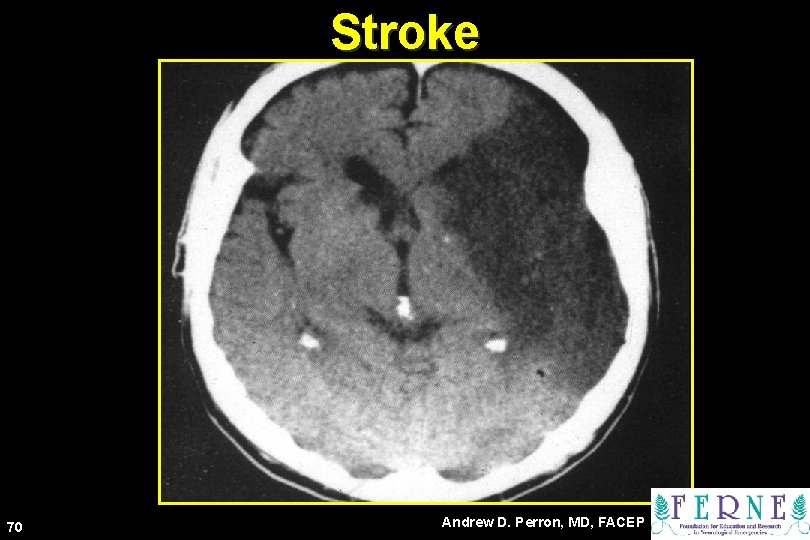

Stroke 70 Andrew D. Perron, MD, FACEP

71 Andrew D. Perron, MD, FACEP

72 Andrew D. Perron, MD, FACEP